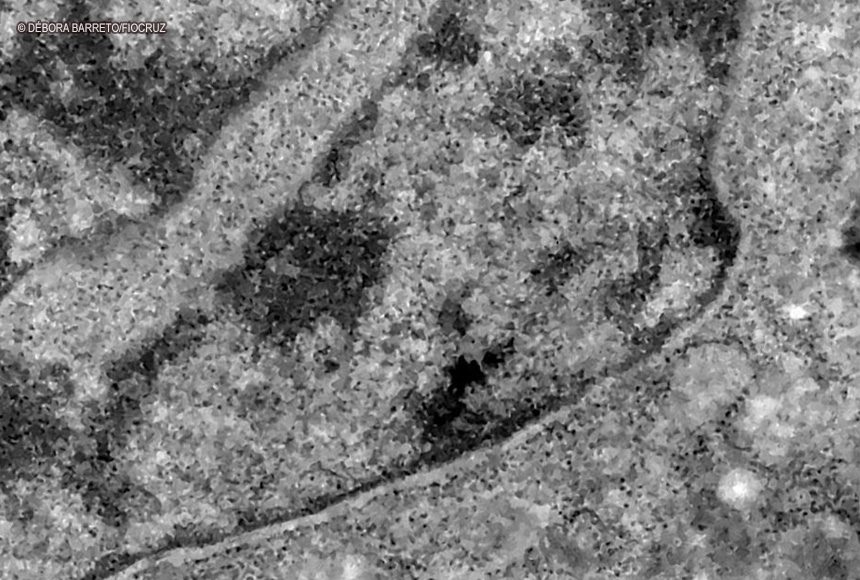

O surgimento de uma variante no novo coronavírus confirmado em regiões da África preocupa especialistas internacionais de saúde. Batizada de Ômicron – letra grega correspondente à letra “o” do alfabeto -, a cepa B.1.1.529 foi identificada em Botsuana, país vizinho à África do Sul, em meados de novembro. Segundo a Organização Mundial da Saúde (OMS), a variante pode se tornar responsável pela maior parte de novos registros de infecção pelo novo coronavírus em províncias sul-africanas.

Nos casos analisados, constatou-se que a variante é portadora de dezenas de mutações genéticas que podem afetar os índices de contágio e de letalidade. A OMS, entretanto, afirmou que ainda não há estudos suficientes para afirmar as propriedades da Ômicron, mas que já existem esforços científicos acelerados para estudar as amostras. Um time de cientistas de universidades da África do Sul está decodificando o genoma da Ômicron, juntamente com dezenas de outras variantes do novo coronavírus.

Tulio de Oliveira, diretor do Centro para Respostas e Inovações Epidêmicas da universidade de KwaZulu-Natal, afirmou em coletiva de imprensa que a variante Ômicron possui “uma constelação incomum de mutações”. A variante Delta, por exemplo, possuía duas mutações em relação à cepa original do novo coronavírus, enquanto a Ômicron possui cerca de 50 – 30 delas localizadas na proteína Spike, responsável por infectar células saudáveis, explicou o brasileiro.